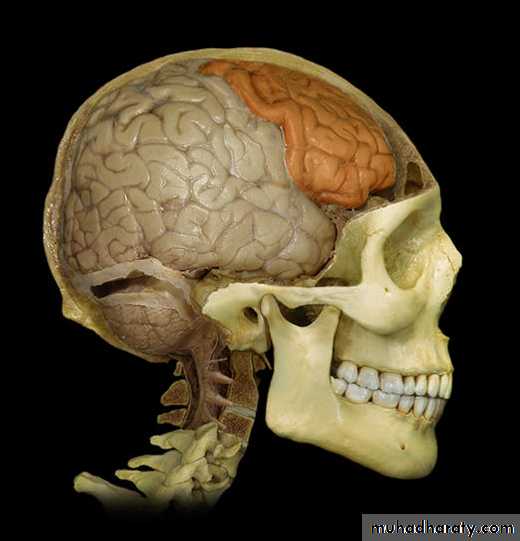

Lobes of Cerebral Hemisphere

Five lobes

Frontal lobe

Parietal lobe

Temporal lobe

Occipital lobe

Insular lobe

Parietal lobeOccipital lobe